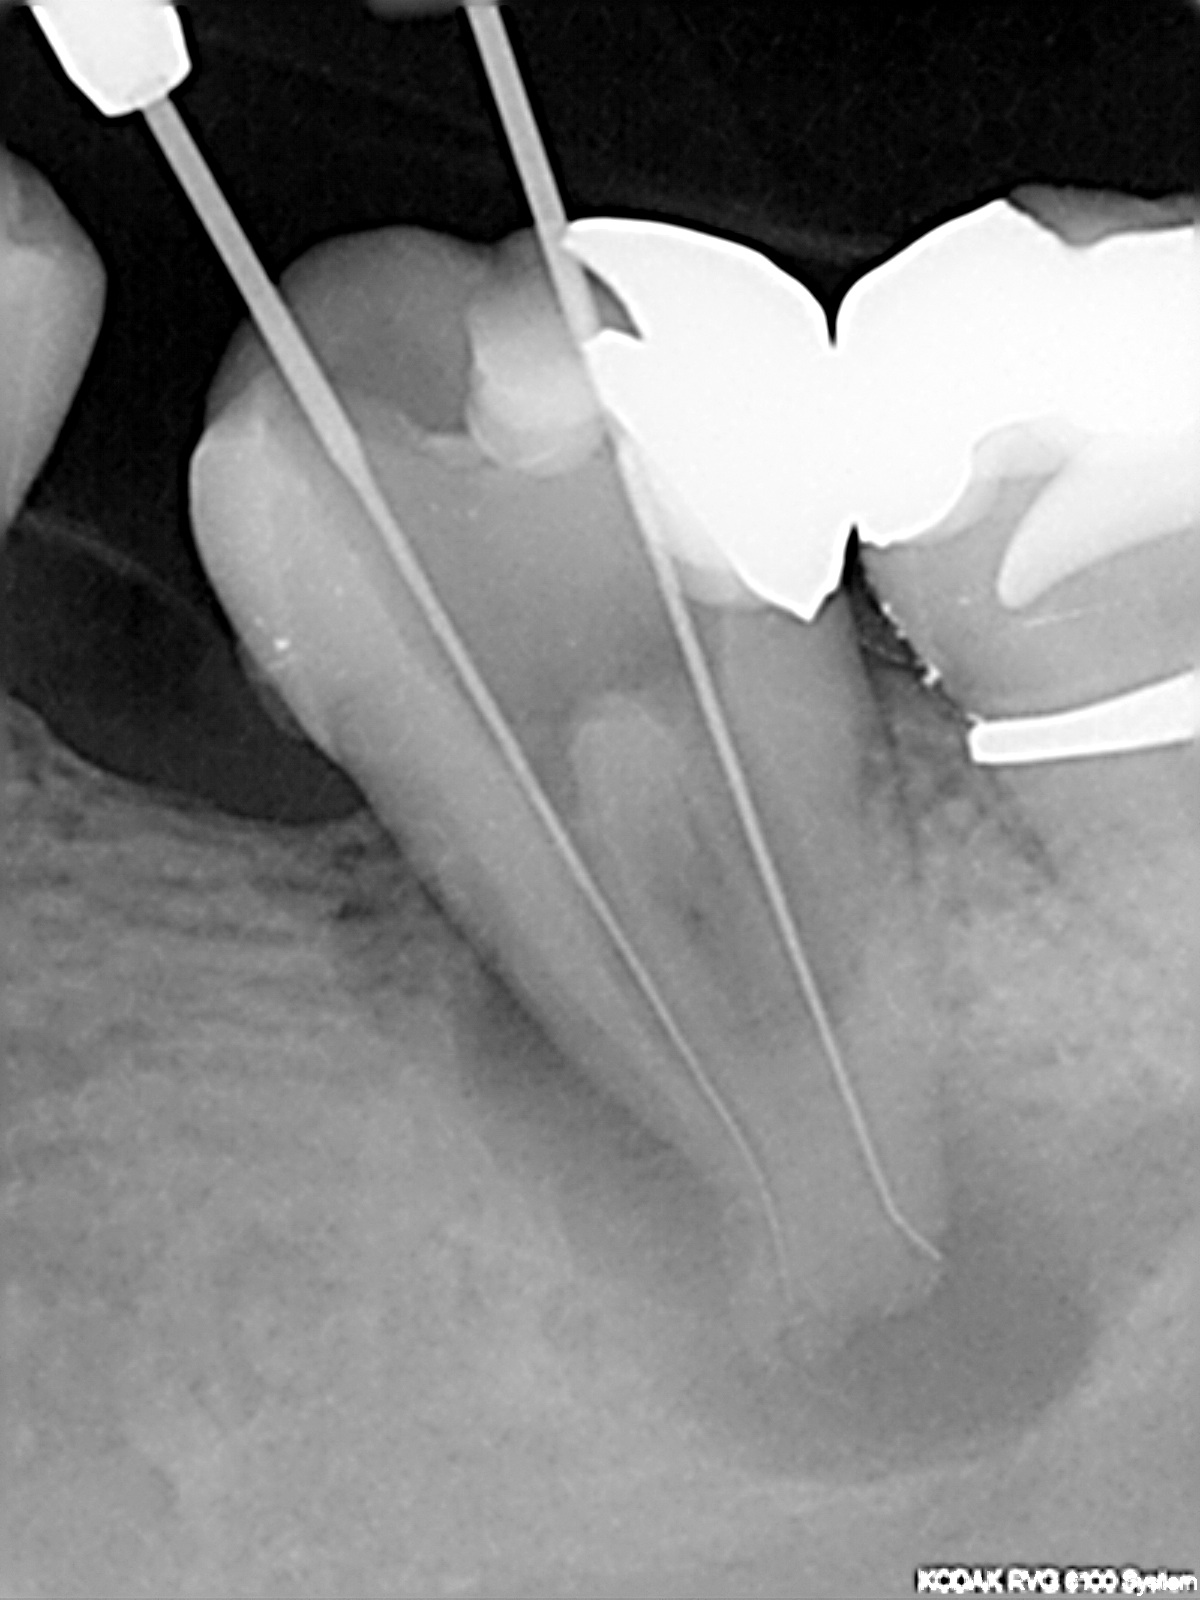

Messaufnahme

Interessante Kanalanatomie (2)